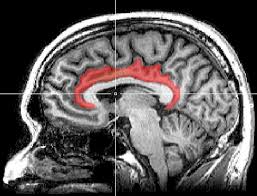

An aneurysm occurs when a blood vessel wall weakens, causing it to bulge or balloon. While some aneurysms remain small and harmless, others can grow silently and rupture, leading to life-threatening complications. The tricky part is that many aneurysms develop without obvious symptoms—so recognizing early warning signs can save lives.

Often called the “worst headache of your life”, this is one of the most common warning signs of a brain (cerebral) aneurysm.

Aneurysms in or near the brain can put pressure on surrounding nerves, leading to:

If an aneurysm presses on nerves or affects blood flow to the brain:

A ruptured aneurysm can cause:

Bottom line: Aneurysms are silent threats that can escalate quickly. Paying attention to unusual pain, neurological changes, or pulsating sensations in the body could save your life. Early detection is the key.